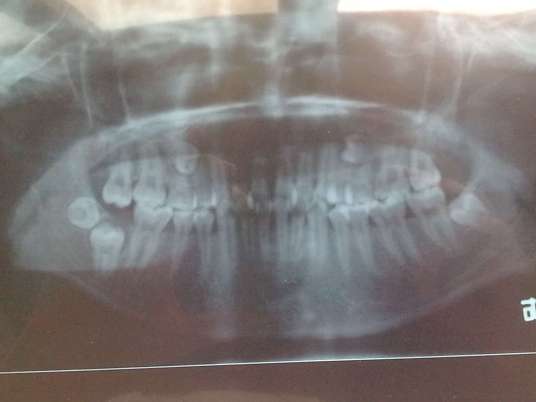

您的位置首页百科知识 埋伏牙 Simone 发布于 2025-11-08 23:00:47 875 阅读 埋伏牙的有关信息介绍如下:牙齿萌出期已过而仍在颌骨组织中未能萌出的牙齿称为埋伏牙(embeded teeth)。想要了解更多“埋伏牙”的信息,请点击:埋伏牙百科